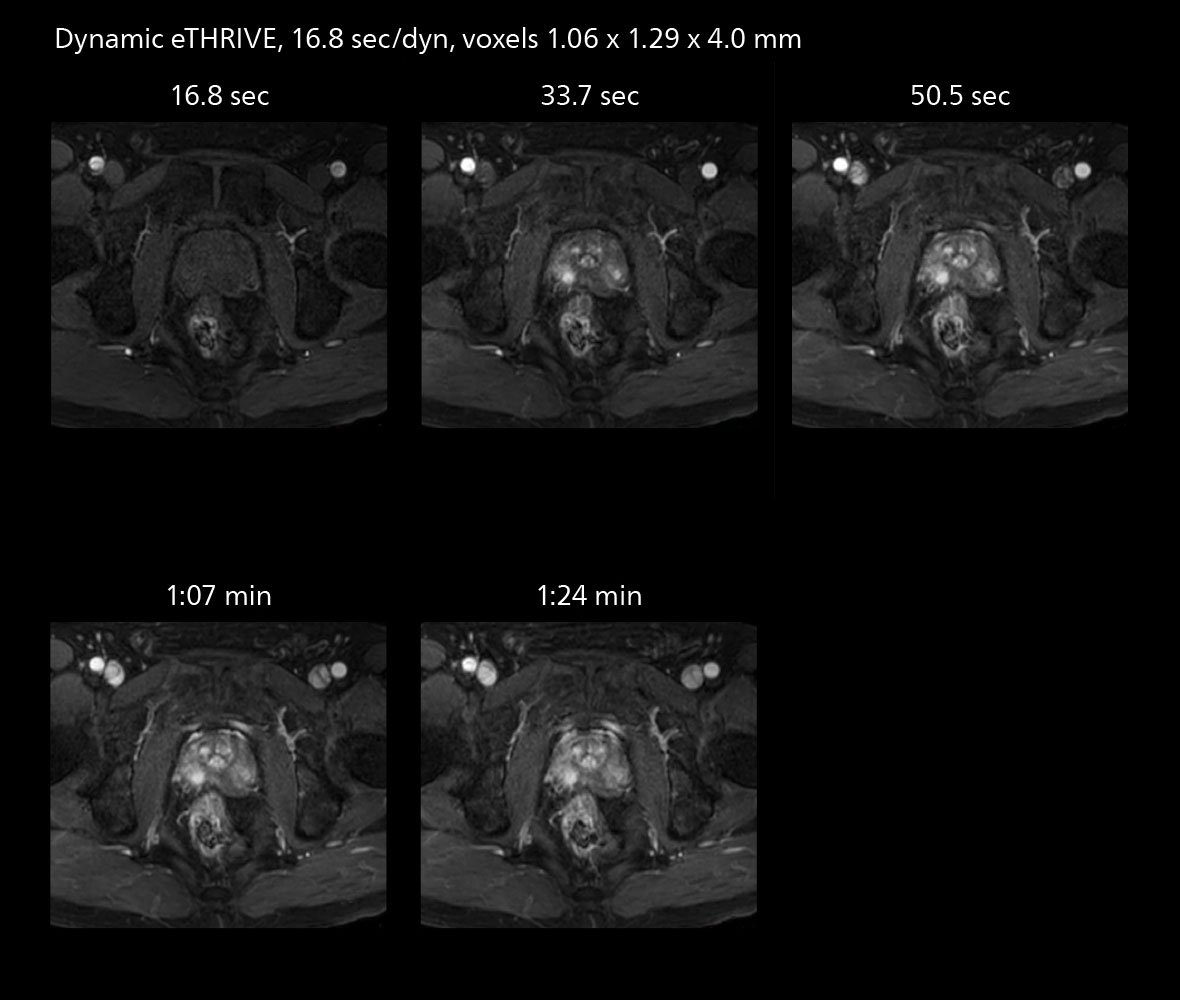

MRI of prostate

Examples of prostate imaging showing faster scan times and improved resolution illustrate the power of SmartPath to Elition X in this case of prostate cancer with PI-RADS score 4.